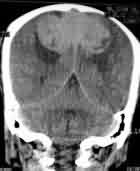

Orbital meningioma-CT